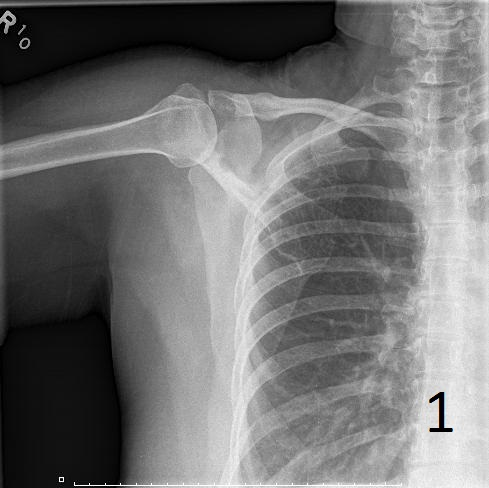

• Lesions are metaphyseal and diaphyseal (Fig. 1)

• Lytic lesion, with a “ground glass” appearance; trabeculae appear smudged as though somebody took a pencil eraser and smudged them

• Affected bone may present with a well defined sclerotic, expanded and thick reactive bone called rind of sclerosis

Fig. 1. AP plain x-ray of fibrous dysplasia of the right shoulder showing an expanded lytic lesion involving the spine of the scapula.